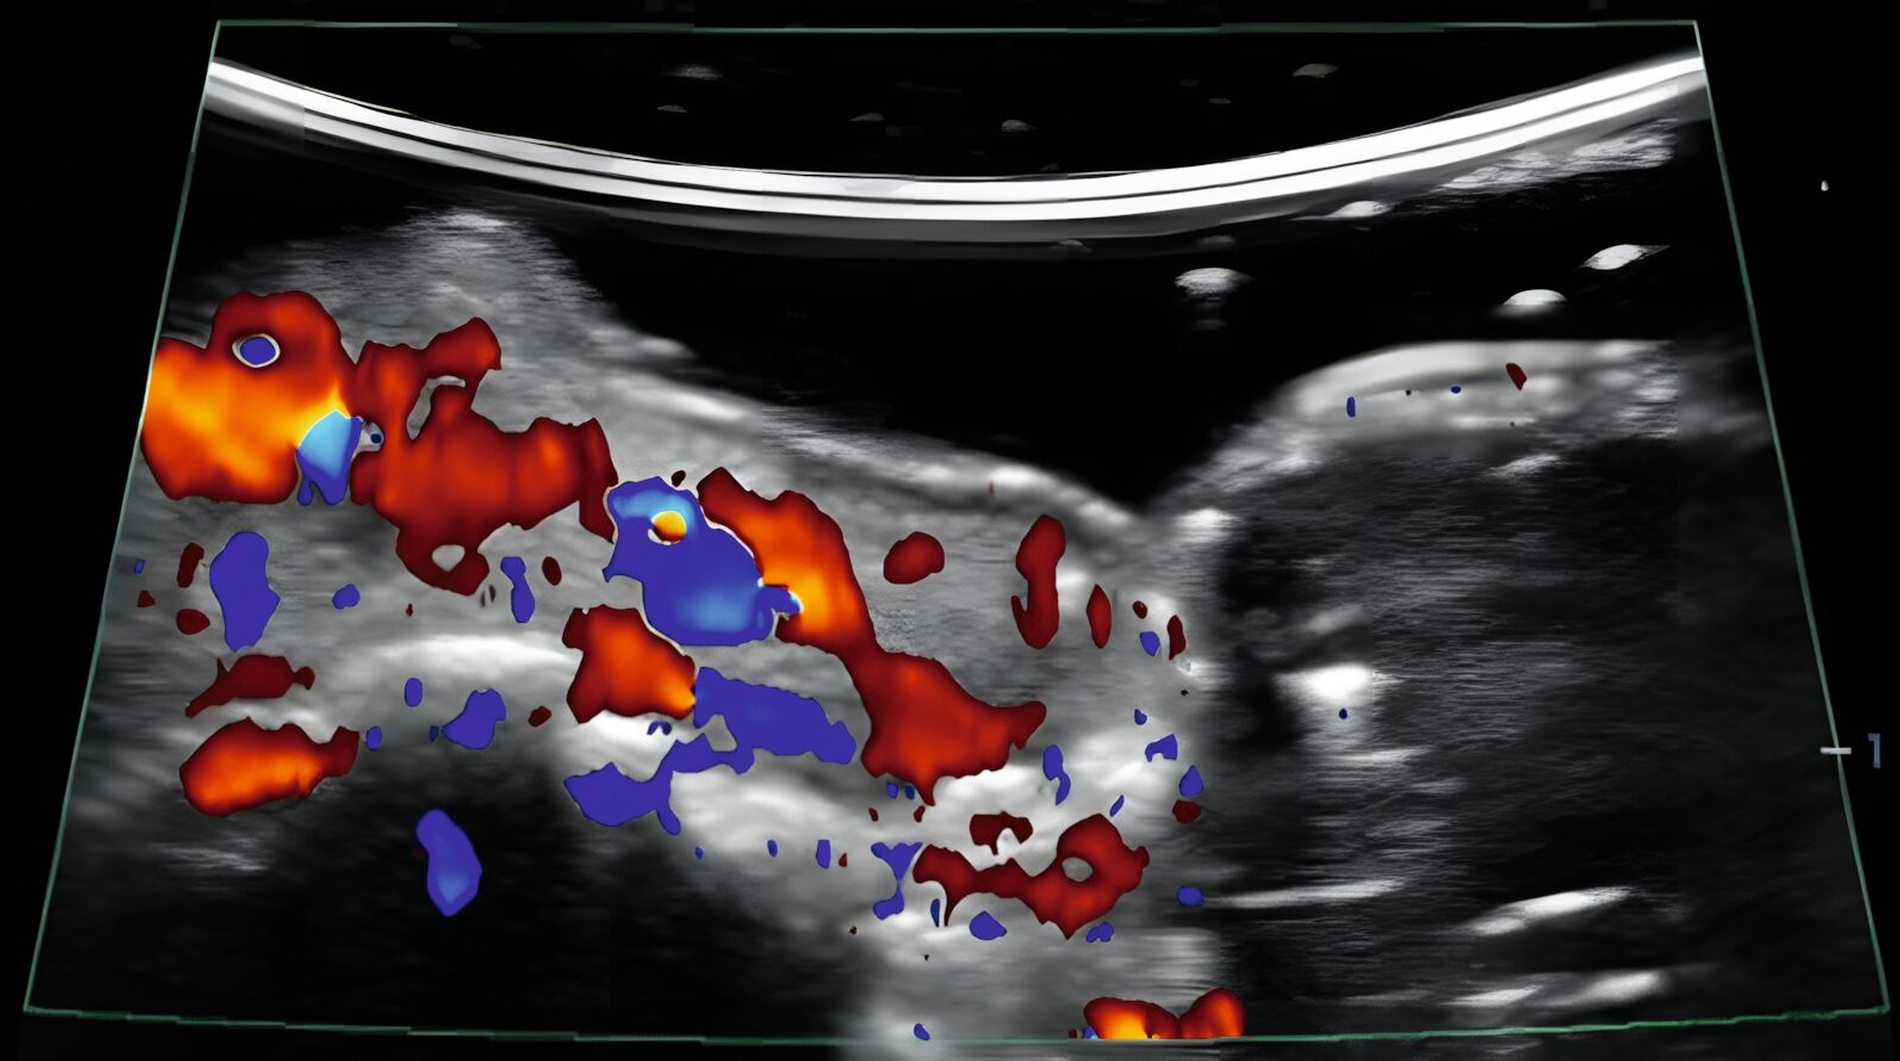

In klinischen Studien konnte gezeigt werden, dass die Sonografie des oralen Weichgewebes zur Beurteilung der dynamischen Gewebeperfusion und von Blutflussschwankungen angewendet werden kann [Chan et al., 2020; Barootchi et al., 2022; Chan & Kripfgans, 2020; Tavelli et al., 2023]. Am Implantat wurde in einer klinischen Studie erstmals mit einer 30-MHz-US-Sonde (ZS3, L30-8, Mindray, Mountain View CA, USA) die Differenzierung zwischen periimplantärer Gesundheit und Erkrankungen beschrieben [Chan et al., 2020] (Abbildung 9).

In einer weiteren klinischen Studie wurde die Aussagekraft der funktionellen Sonografie des periimplantären Weichgewebes bei Implantaten mit unterschiedlichen klinischen Diagnosen (gesund, periimplantäre Mukositis oder Periimplantitis) untersucht [Barootchi et al., 2022]. Der US-Farbfluss konnte die periimplantäre Durchblutung messen und die US-Messungen stimmten mit den klinischen Diagnosen überein.

Zusammenfassend zeigen die Ergebnisse, dass die funktionelle Sonografie (Gewebeperfusion und Blutflussschwankungen) zur Differenzierung des oralen, weichgewebigen Entzündungsgrades angewendet werden kann.

Neben der anatomischen Darstellung wird auch die funktionelle Bildgebung zur Beurteilung der Gewebedurchblutung mittels Farbfluss (traditionell Farb-Doppler genannt) intensiv untersucht. In klinischen Studien konnte die Sonografie zur Differenzierung parodontaler und periimplantärer Erkrankungen erfolgreich angewendet werden.